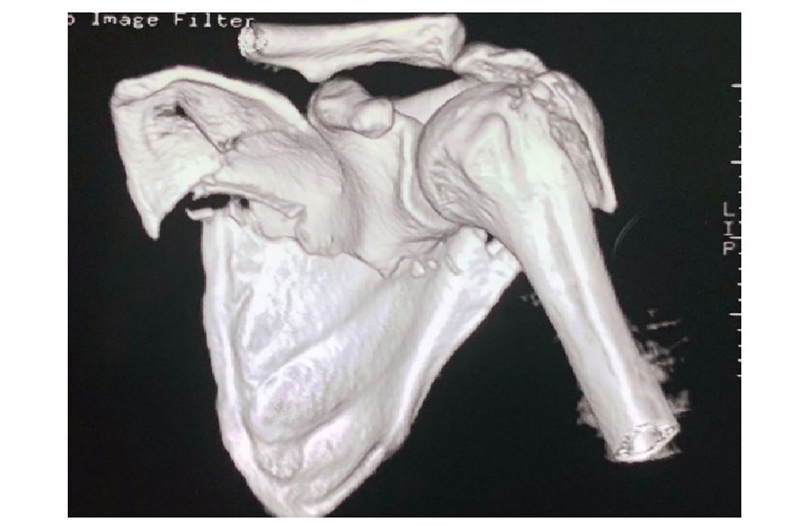

病例4为53岁男性患者,因高处坠落导致右肩胛骨骨折,合并右侧第3、5、7、8肋骨骨折(图20-21)。

图20 术前X线片示肩胛颈及肩胛骨体部骨折

图21 术前CT三维重建示肩胛颈及肩胛骨体部骨折 图A:肩胛骨前面观;图B:肩胛骨侧面观

术中采用钢板固定肩胛颈内下方骨折块,肩胛骨体部骨折固定采用缝线辅助固定技术,骨折端以Nice结固定。术后CT三维重建显示骨折复位满意,固定良好(图22)。